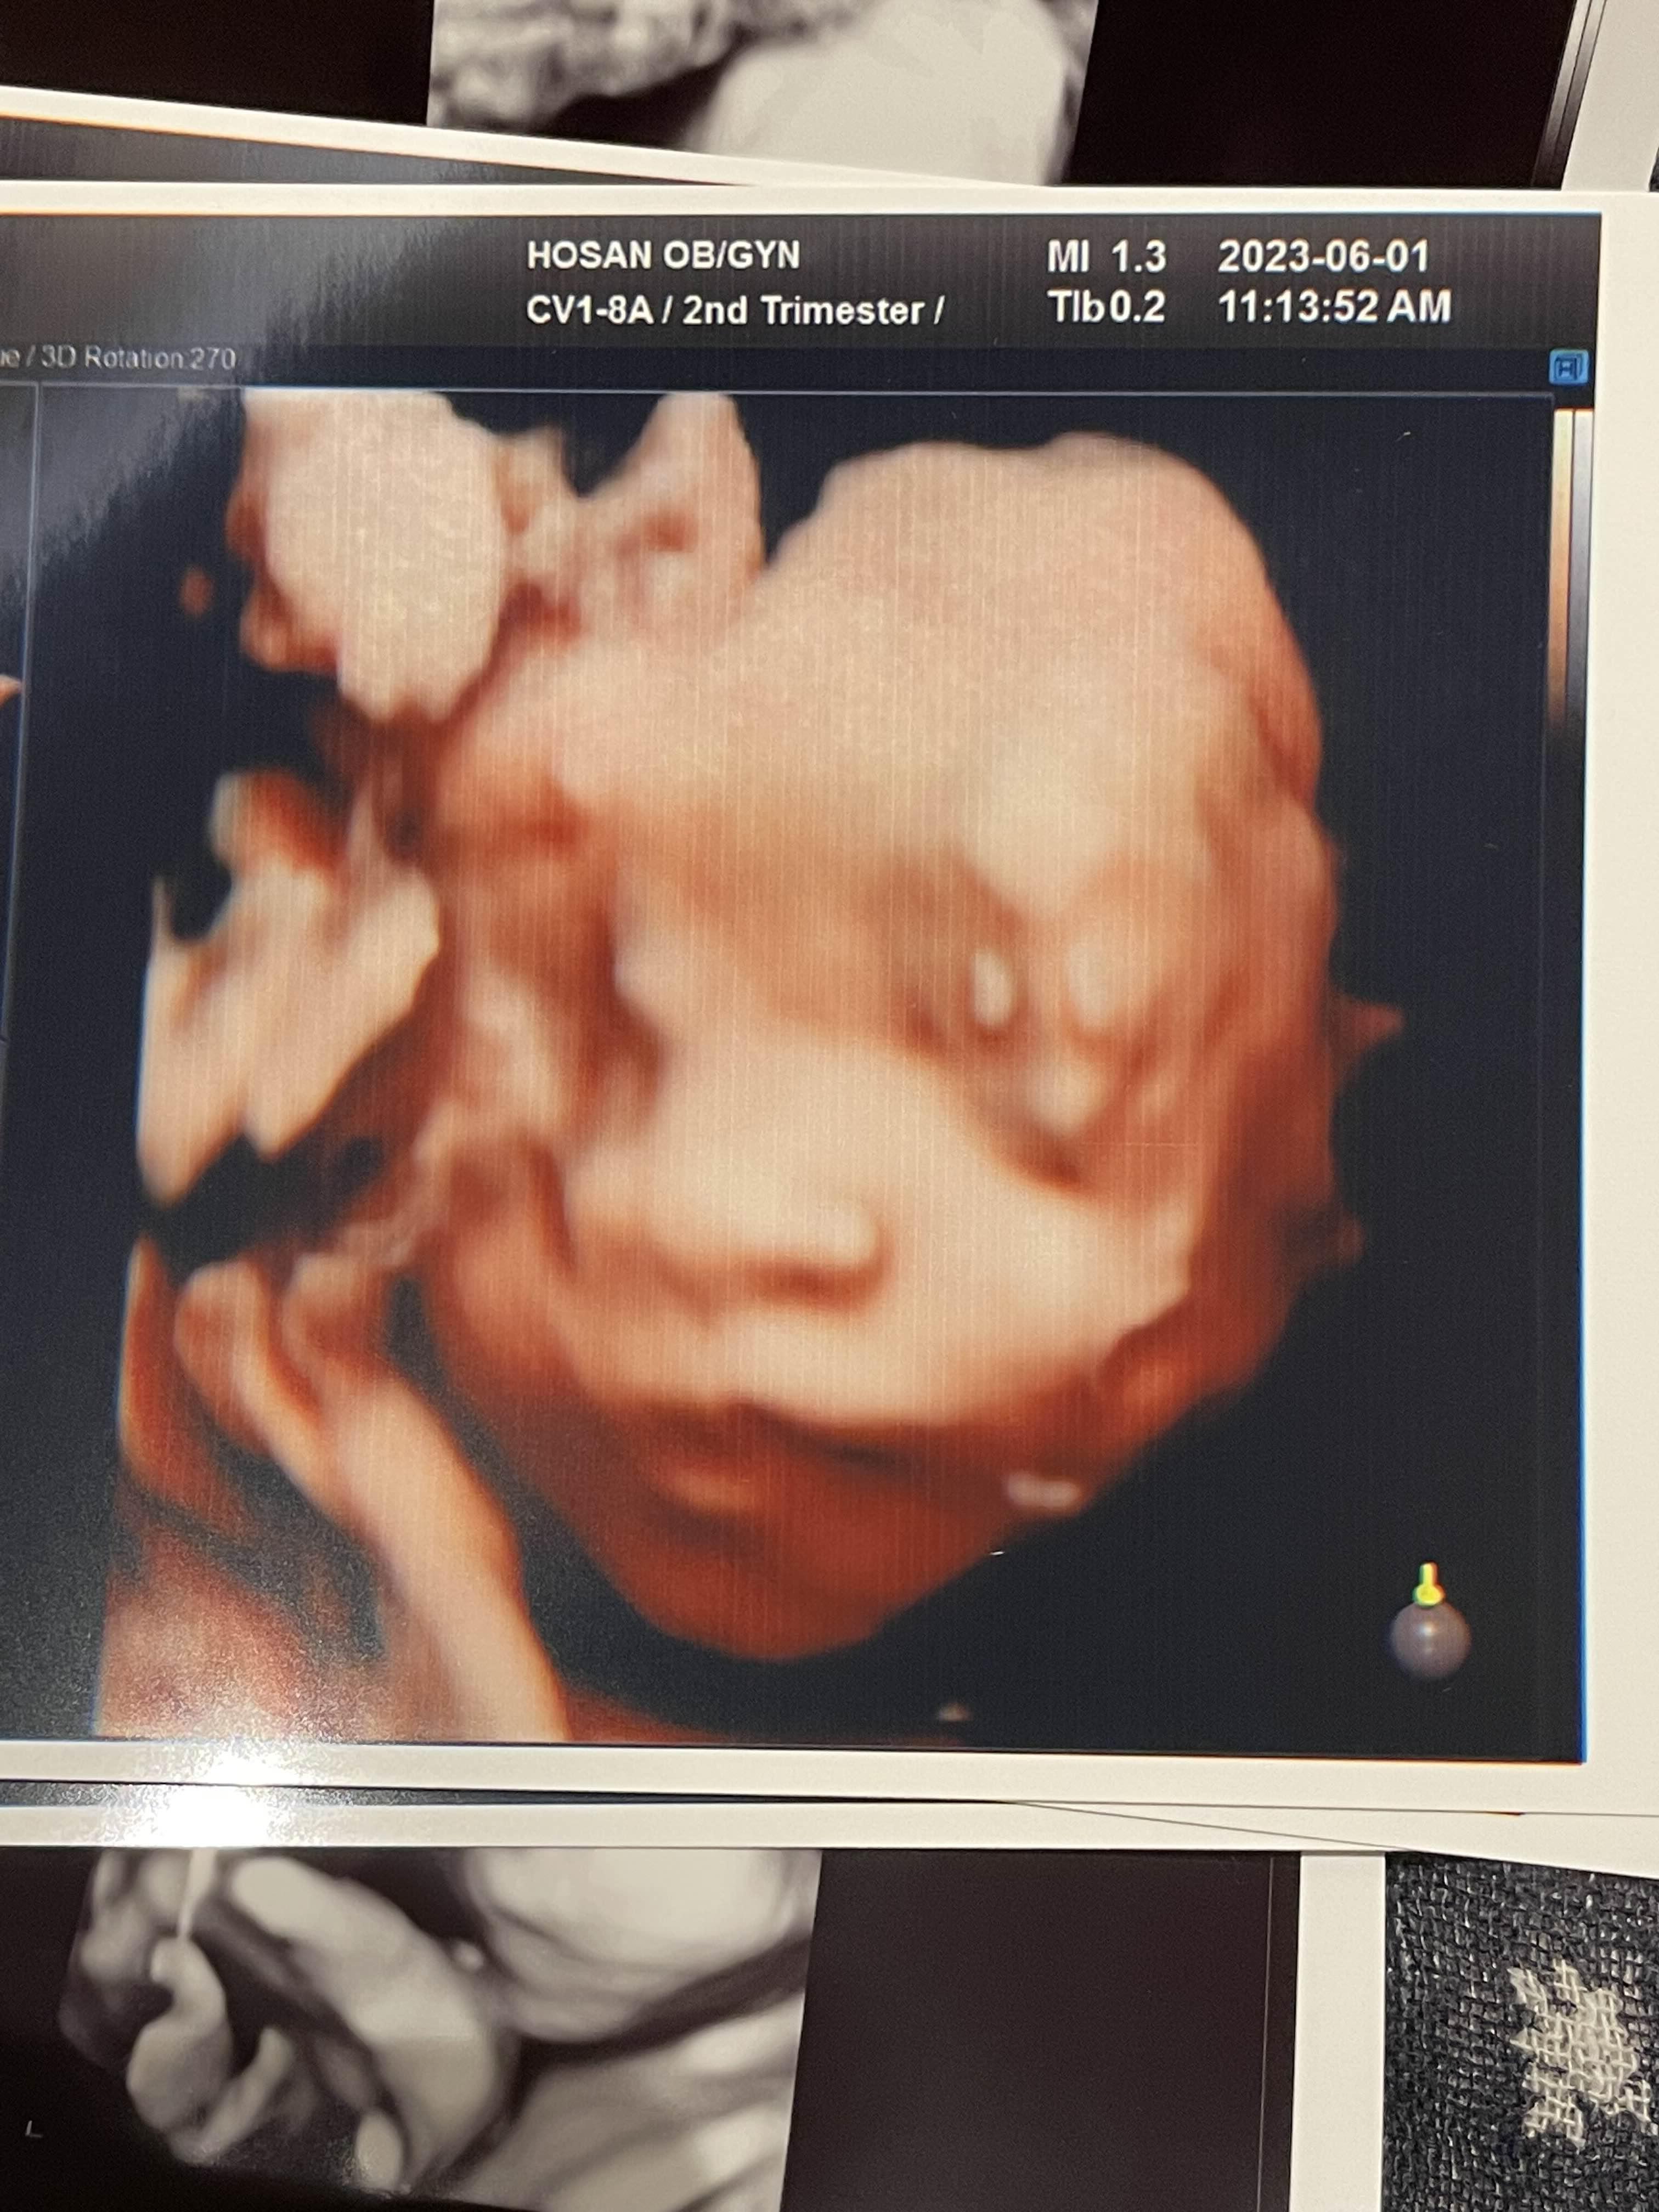

병원 간 김에

귀여운 우리 애기 얼굴도 보고 왔어요~

입술이 뭔가 아빠를 닮은 느낌이ㅎㅎ

제발 눈은 엄마눈 닮자 우리 공주님~!